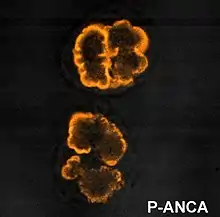

Serum analysis often aids in the diagnosis of a specific underlying disease. The presence of anti-glomerular basement membrane (GBM) antibodies suggests type I RPGN; antinuclear antibodies (ANA) may support a diagnosis of systemic lupus erythematosus and type II RPGN; and type III and idiopathic RPGN are frequently associated with anti-neutrophil cytoplasmic antibodies (ANCA)-positive serum.[2]

RPGN can be classified into three types, based upon the immunofluorescence patterns:[3]

Also known as pauci-immune RPGN, type III RPGN accounts for 55% of RPGN and features neither immune complex deposition nor anti-GBM antibodies. Instead, the glomeruli are damaged in an undefined manner, perhaps through the activation of neutrophils in response to ANCA. Type III RPGN may be isolated to the glomerulus (primary, or idiopathic) or associated with a systemic disease (secondary). In most cases of the latter, the systemic disease is an ANCA-associated vasculitis such as granulomatosis with polyangiitis, microscopic polyangiitis or eosinophilic granulomatosis with polyangiitis.[2]